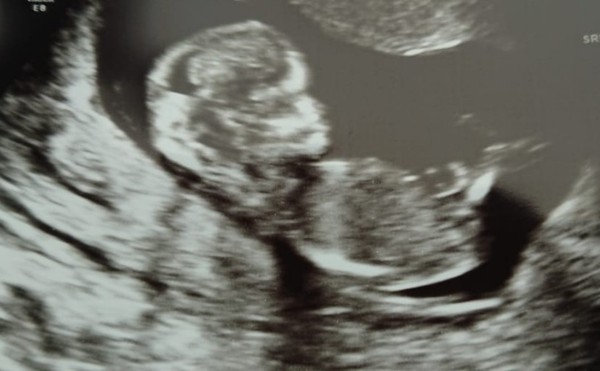

Scan all ok! Baby wouldn't oblige too much but they got what they needed in the end!